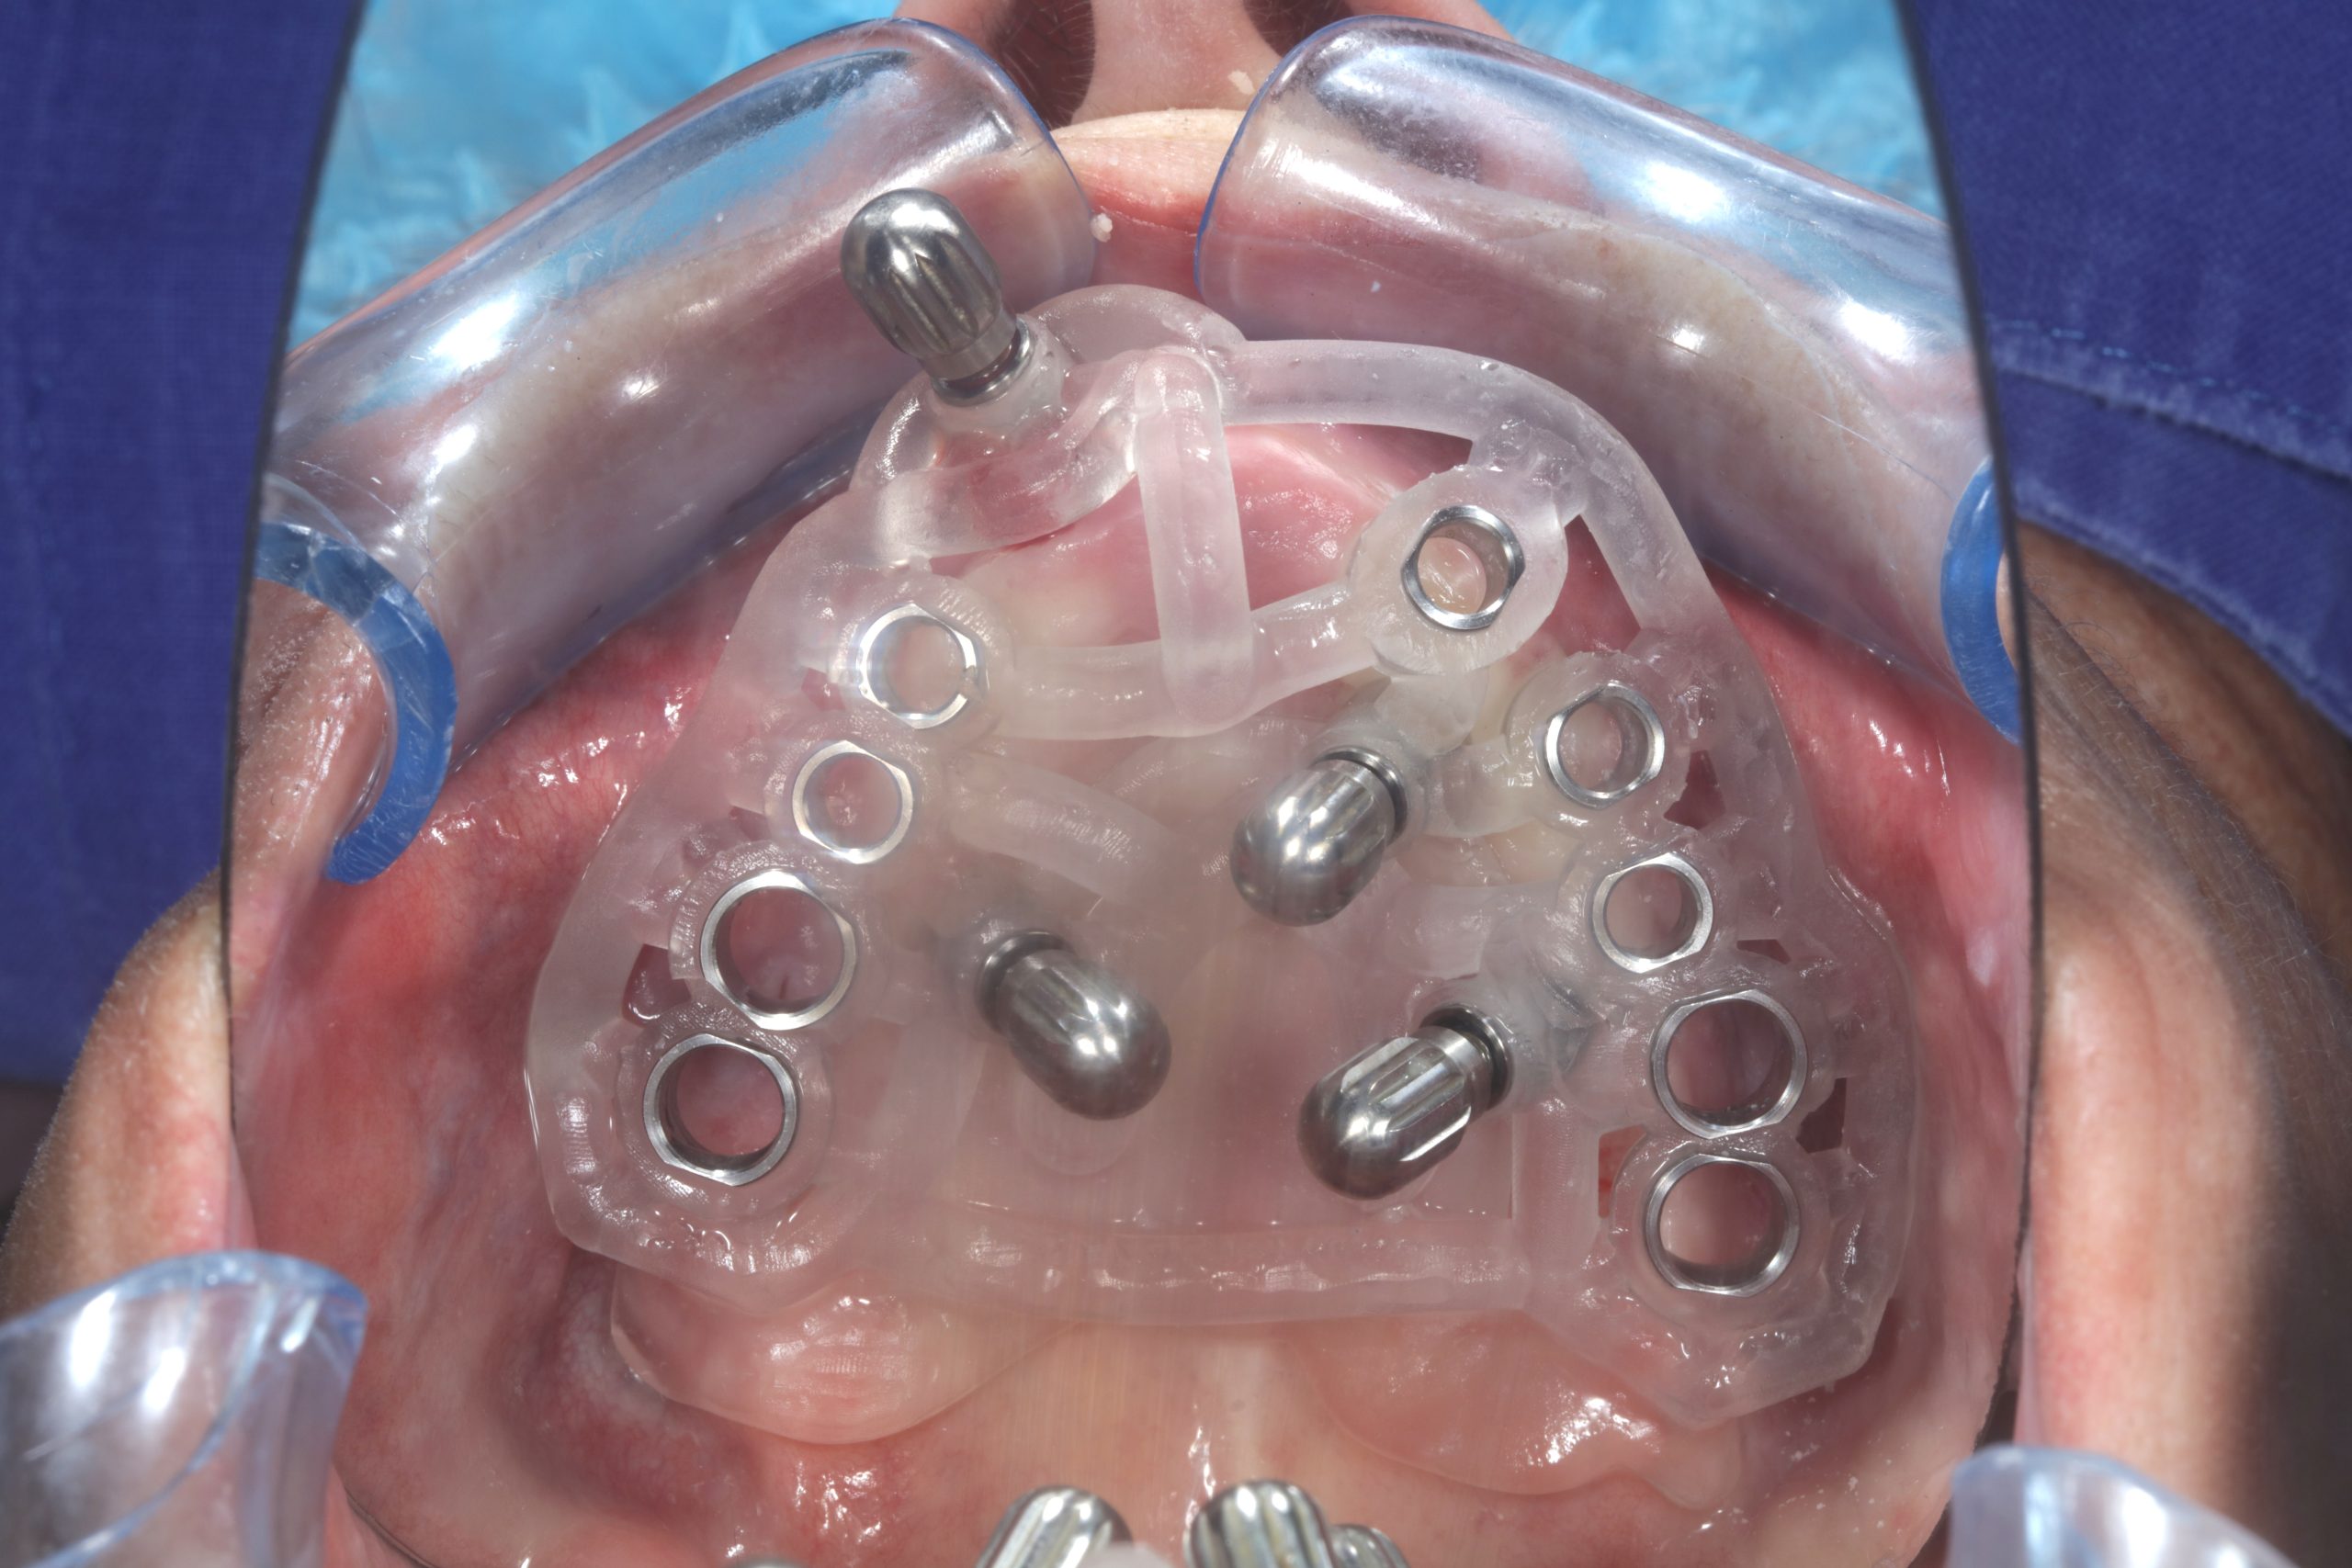

The use of CDP (Complete Digital Patient) as a basis for planning in a case of complete implant rehabilitation with a full arch in zirconia – ceramicised

Case study carried out with Athena Smile Pelekanos (GR ) : dott . Stavros Pelekanos